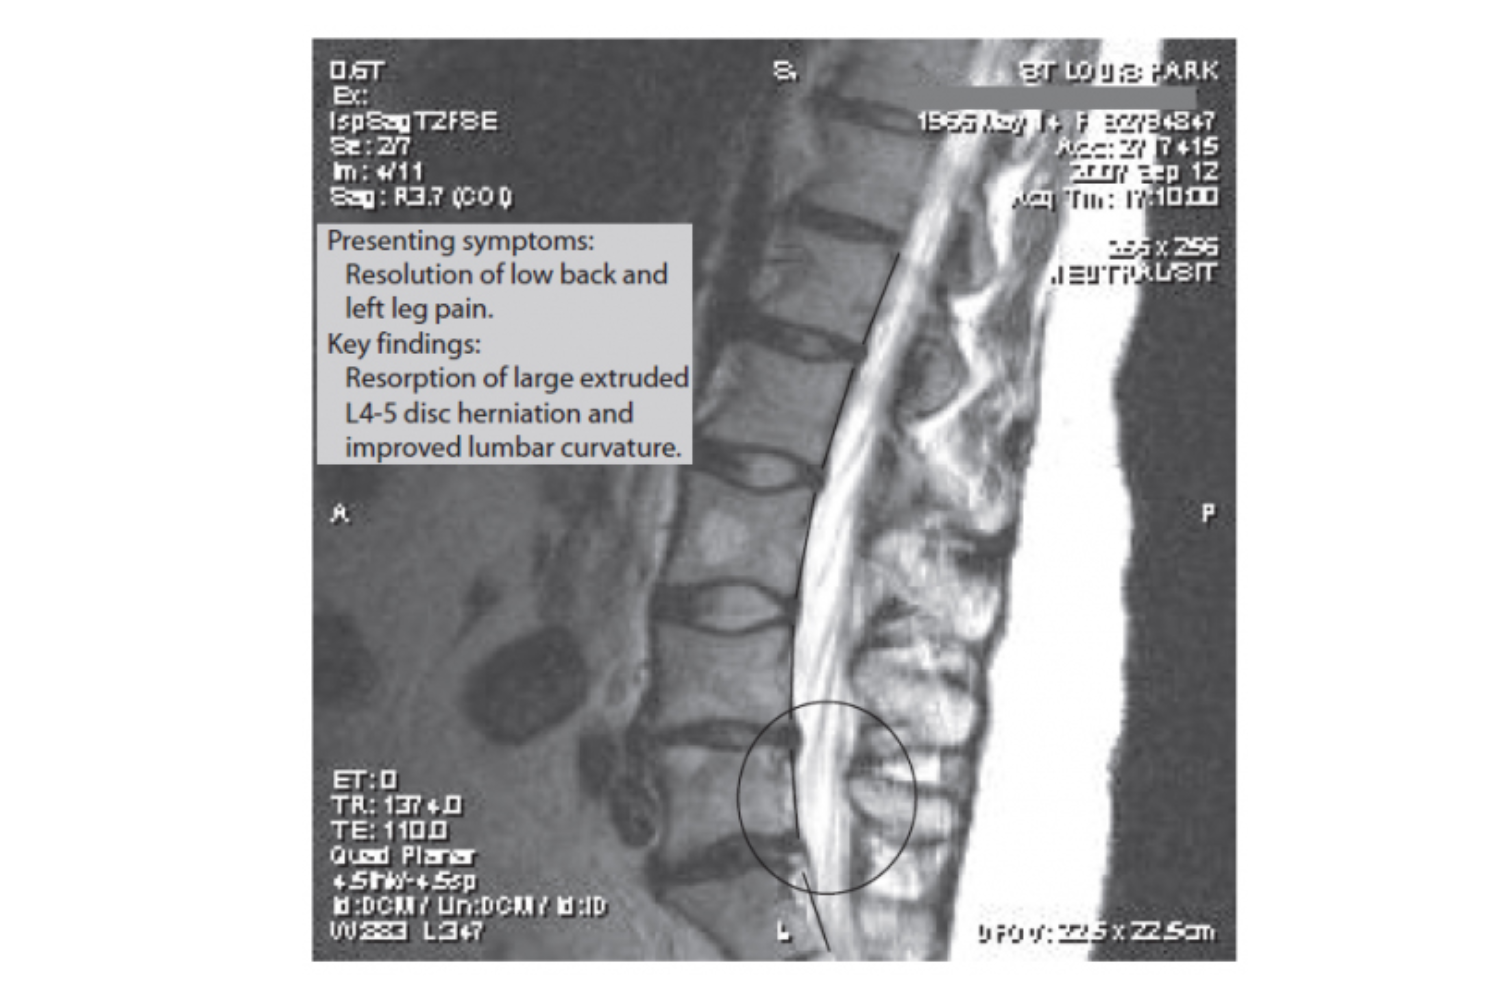

Radiologist Interpretation: There is a large disc herniation extruding caudally on the left downward from L4-5 to nearly the inferior L5 endplate. This measures 21 mm in cephalocaudad dimension by 10 mm in AP dimension and markedly compresses the left L5 nerve root sleeve at the subarticular and lateral recess.